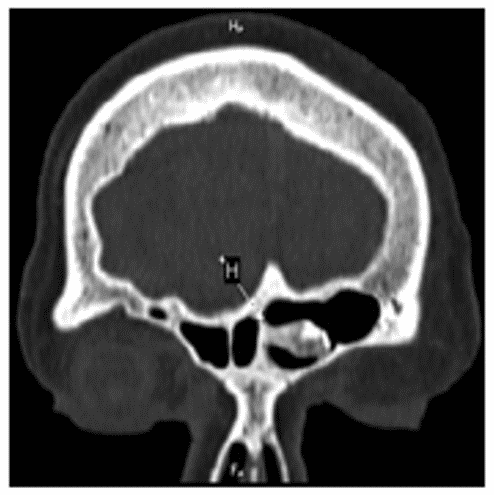

По данным компьютерной томографии такие остеомы состоят из двух зон: зоны плотностью 300 - 600 ед. Н, имеющей губчатое строение, и зоны плотностью более 800 ед. Н, имеющей структуру компактного костного вещества. Четкая граница между указанными зонами отмечается не всегда, иногда имеет место постепенное повышение коэффициентов поглощения костной ткани (рисунок 3).

Рис. 3. КТ околоносовых пазух: аксиальная (А) и коронарная плоскость (Б). Остеома левой лобной пазухи смешанного типа, исходящая из межпазушной перегородки. Обозначения: компактное костное вещество (КВ), ножка опухоли (Н). В области ножки присутствует губчатое вещество, а на периферии опухоли - более зрелое компактное костное вещество